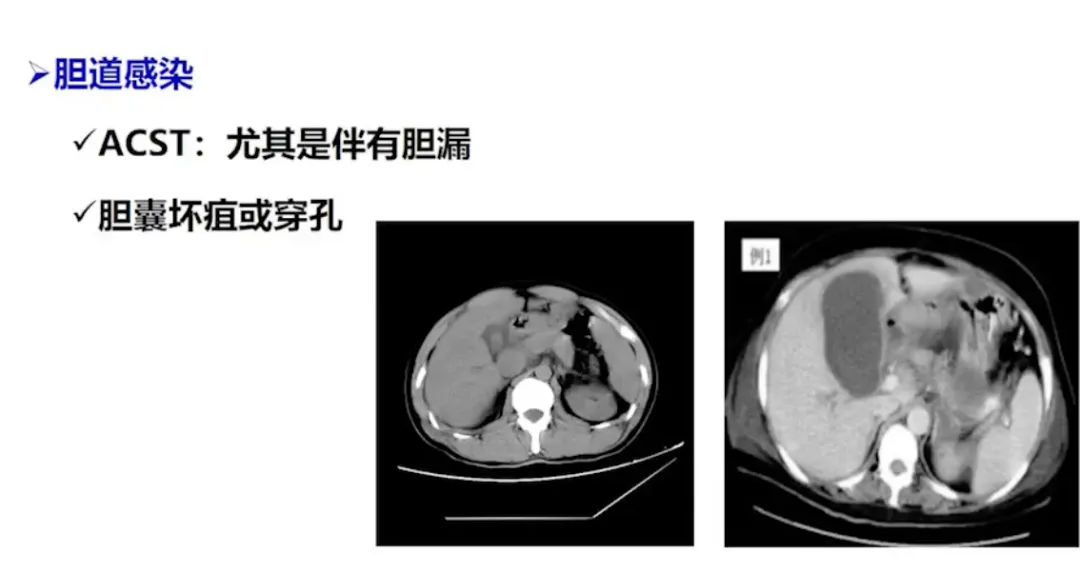

脓毒症的处理